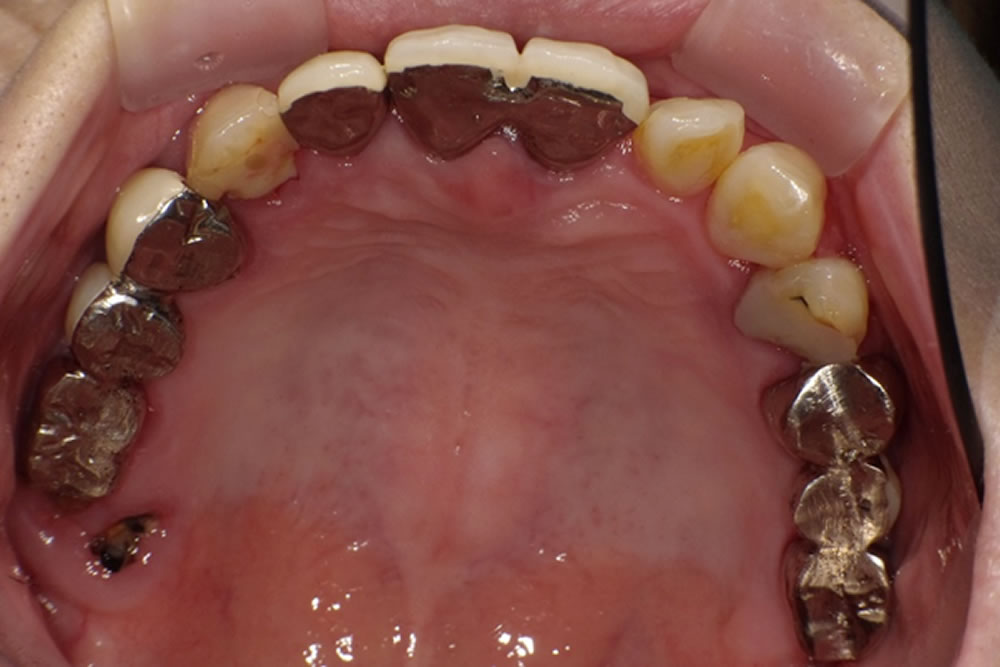

保存不可能なブリッジ部分を抜歯後にインプラントで治療した症例 こちらの患者さまは、過去に治療した右上ブリッジの違和感を主訴で来院されました。 初診時の口腔内 右上奥歯部分に3本分のブリッジが入っていましたが、ブリッジと歯 […]